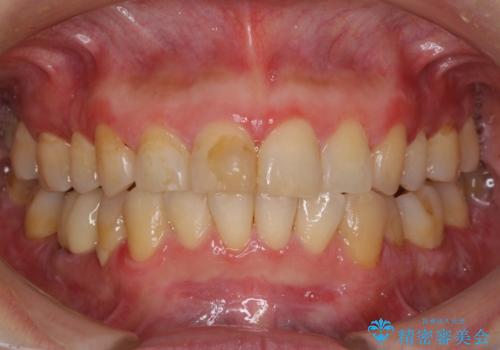

- 昔ぶつけて欠けた前歯をきれいにしたい、とご来院された患者様です。

プラスチックの詰め物が長年の劣化により変色していました。

前歯2本のラミネート治療をご希望でしたが、前歯の見た目が悪いのは右上前歯1本が原因であり、左上前歯は虫歯などがなく、削るのはもったいないということをご説明しました。

また、右上の前歯は裏側までヒビが入っていることや、1層構造のラミネートよりも2層構造のオールセラミッククラウンの方が色の再現性も高いことから、右上前歯1本のクラウン治療をおすすめしました。

今回は、歯肉炎があるため、その治療を行ってからクラウンを製作しました。

歯肉炎がない場合は、1か月ほどで治療が完了します。逆に、炎症がひどい場合は、治療期間が長くなります。